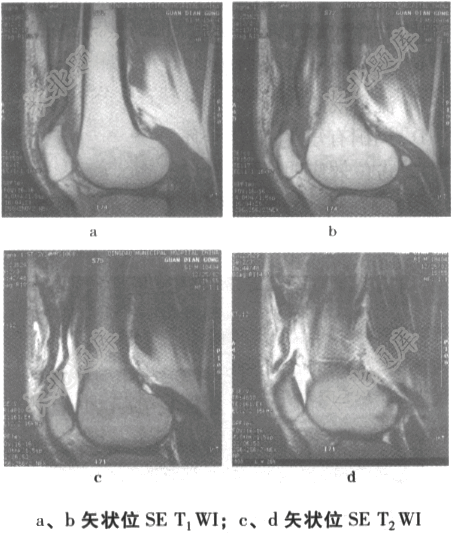

- 单项选择题男,61岁,右膝部外伤3个小时,右膝肿痛。结合右膝部MRI扫描片,最可能的诊断是为

A、内侧半月板撕裂

B、股骨下端骨挫伤

C、股骨下端撕脱骨折

D、股四头肌肌腱部分撕裂

E、外侧半月板撕裂